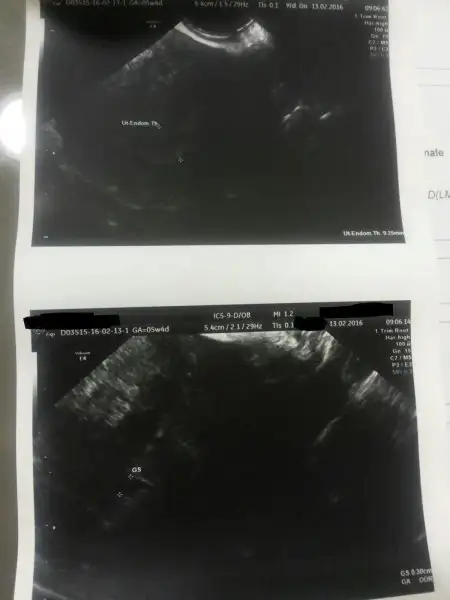

boyle bı betalarım var, 5+4 gunlukken rahımde 3 mm bos kese gozlendı ama doktor rapora bunu kıst olarak gırmıs kıst gorunumlu duzensız sınırlı gıbı bısıler yazıyor. Dıs gebelıkte belırtı varmı ? bu kadar anlasılması zor bısey mı cumartesı vajınal usg yapıldı bu hafta yıne bakılacak. progesteron 13 şubatta 8.7 cıktı normal dedıler bunada hatat cumartesı aksamı cıkan sonucları doktor mukemmel bulmustu.

agrım yok kanamam yok nedır bu yasadıgım ?

cunku daha sonra gıttıgım dr kese var dedı bana karından gordu bu seferde ama ıcı bos oldugu ıcın kıst olarak degerlendırılıyor anekoıkmı neymıs.

İşte doktorun verdikleri